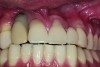

Buccal soft tissue recession which occurred 1 year following completion of the implant restoration is another example of a reversible complication.

Figure 3

The implant restoration and surrounding soft tissue seen in Fig 3, 5 years following treatment.

Figure 4